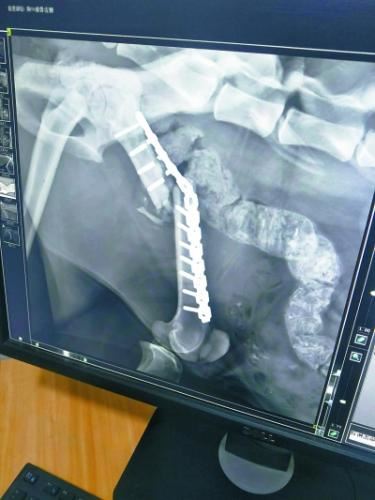

第一次手术植入的钢钉折断了3根

考虑到“凌雪”年事已高,已经打过11根钢钉,再次利用钢钉的话,可能会骨骼碎裂。而产生的碎骨还可能对肌肉等组织造成二次伤害,甚至感染致命。西宁野生动物园曾组织兽医和动物医院的医生进行了讨论,又向青海三甲医院的骨科专家进行了咨询,同时还向国内资深的野生动物救护人员、动物园兽医求教,但大家的意见差别很大。

最后,在收到了海内外数十位专家、学者的反馈后,西宁野生动物园最终选择由北京派仕佳德动物医院的姚海峰博士主刀,为“凌雪”进行二次手术。

说到选择姚博士的原因,齐园长说,姚博士建议在二次手术时,用质量更好的骨板+髓内钉固定的方案,获业界认可。而且,他在得知雪豹救护的事情后,主动提出手术费用全免,展现了其关爱野生动物的情怀,也为动物园减轻了巨大的经济压力。